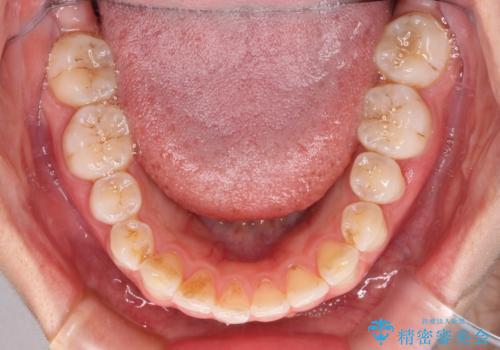

前歯の捻れを改善 インビザラインによる矯正治療

- 前歯の翼状捻転を気にして来院された患者様です。

全体的に叢生は軽度であったため、インビザラインにて矯正治療を行うこととしました。

前歯の幅の大きさも気になっていたため、IPRにより叢生を解消するとともに、歯の大きさも改善しました。